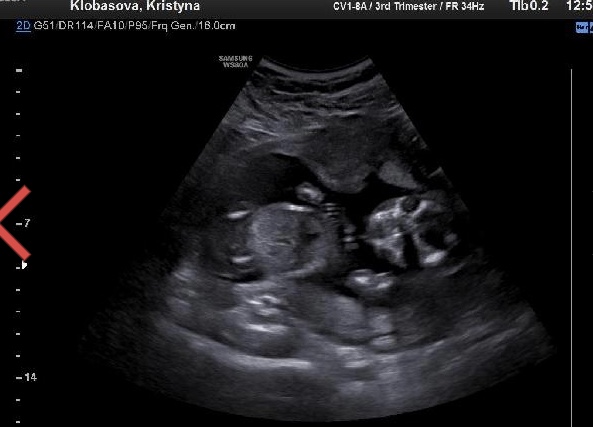

@erika63 včera som bola 16+4